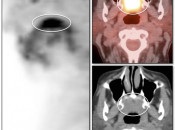

To this end, considerable attention will be made in later chapters to:

- Normal Structures that are FDG-Avid [Chapter 5] [Fig. 3]